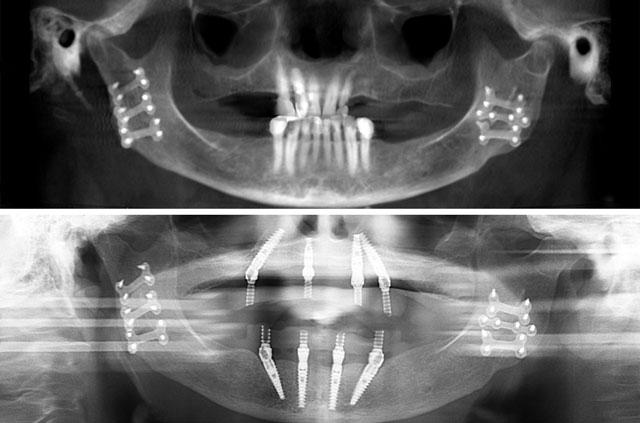

All-on-4 is a revolutionary dental implant technique that uses just four strategically placed implants to support a full arch of replacement teeth. The posterior implants are angled at 30-45 degrees to maximize bone contact and avoid anatomical structures like the maxillary sinus or inferior alveolar nerve. This innovative approach allows for immediate loading with a temporary prosthesis, providing same-day teeth and eliminating the need for lengthy healing periods between procedures.